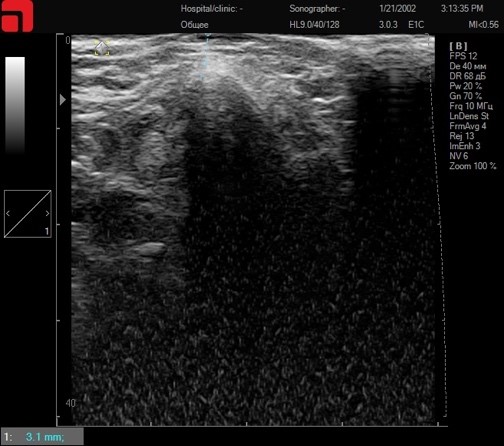

Соединительная ткань при установке каппы и сильном надавливании на манипулу

Рис. 3. Соединительная ткань при установке каппы и сильном надавливании на манипулу.

Итак, установив каппу и сильно надавливая на манипулу, манипула 4,5 мм D4 будет работать с соединительной тканью SMAS-слоя, что значительно повышает эффективность процедуры. Интенсивность надавливания на манипулу, а также использование дополнительных инструментов может напрямую влиять на глубину расположения соединительной ткани, так как работа ведется с мягкими тканями, которые можно распластать, влияя на глубину их расположения. Таким образом, при проведении ультразвукового сканирования кожи перед процедурой оценивается интенсивность надавливания на манипулу для оптимального попадания по целевым структурам.